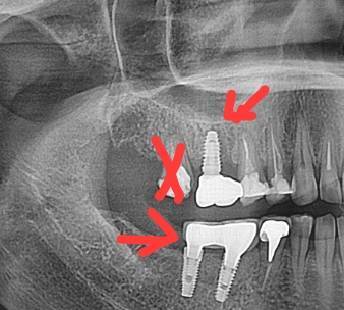

annda Опубликовано 15 марта, 2025 Поделиться Опубликовано 15 марта, 2025 Если не найдете врача, который возьмется за эндодонтию и протезирование, тогда и думайте про удаление этих зубов. Про порядок действий я не могу вас заочно консультировать. Такие планы в принципе только очно составляются.Многое зависит от успешности перелечивания зубов. Кстати, на представленном панорамном фрагменте никаких особых множественных кистогранулем я лично не вижу. . Возможно, они видны на других срезах, на этом обычный периодонтит.А , возможно, что то с глазами у меня не то:)) Ссылка на комментарий

Doc Опубликовано 16 марта, 2025 Поделиться Опубликовано 16 марта, 2025 Как-то все кардинально — все удалять! По одному плоскому снимку сложно что-то советовать. Нужно сделать КТ и показать хорошему специалисту. Ссылка на комментарий

red_butler Опубликовано 16 марта, 2025 Поделиться Опубликовано 16 марта, 2025 32 минуты назад, Doc сказал: Как-то все кардинально — все удалять! По одному плоскому снимку сложно что-то советовать. Нужно сделать КТ и показать хорошему специалисту. +1 и пока не увидел показание к удалению импланта Ссылка на комментарий

Doc Опубликовано 16 марта, 2025 Поделиться Опубликовано 16 марта, 2025 7 минут назад, red_butler сказал: +1 и пока не увидел показание к удалению импланта Вот и я о том. Я бы начал с того, что снял коронку и посмотрел как себя поведут ткани после этого. В любом случае, сначала КТ. 1 Ссылка на комментарий

руслана Опубликовано 16 марта, 2025 Автор Поделиться Опубликовано 16 марта, 2025 (изменено) Имплант вместо 16 в плане лечения стоит на удаление.ставили одномомоментно без пластик.. Необиотек. Пол года назад удален 17 зуб был с передонтитом. Прошлый врач на 17 поставил коронку начались боли. Плюс он стал упираться в нижнюю десну. 47 и 46 инпро. Ноет десна. 24 и 26 имплантация мисс три месяца назад. Имплант 36 удален. Оголился после установки коронки . Был установлен на место давно отсутствующего зуба без пластик. Причинял сильный дискомфорт. Удалили имплант сделали костную с бугра 18. Заживает. Изменено 16 марта, 2025 пользователем руслана Ссылка на комментарий